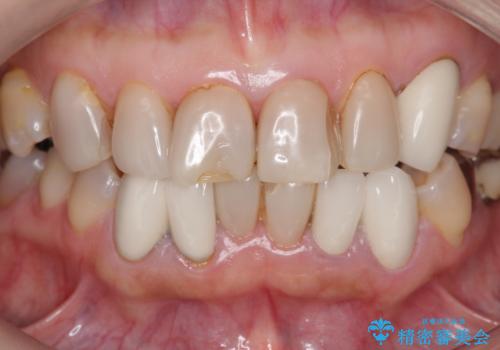

- 上下顎前歯部の見た目が気になるといらっしゃった方の症例です。

上顎は左4番から右4番までの8歯、下顎は左3番から右3番までの6歯、計14歯をオールセラミッククラウンにより補綴しました。